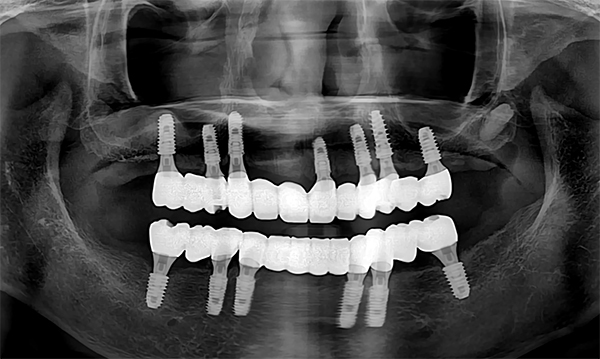

암을 이겨내시고 전악 임플란트를 진행하신 62세 환자분의 사연.

이번 케이스는 기나긴 암치료 때문에 치아 건강이 좋지 않으심에도

불구하고 제대로 관리가 되지 않아서 치아 전체가 망가져서 작년 6월에

처음 내원하신 62세 여성분입니다.

처음에 오셨을때 남길 수 있는 치아가 없을정도로 치주염도 심하시고 파절과 마모가

엄청 심했지요.

마지막 보철 셋팅까지 딱 1년이 걸렸습니다.

그 결과 보철도 너무 튼튼하고 심미적으로도 매우 예쁘게 나와서

환자분께서 많이 기뻐하셨던 기억이 납니다.